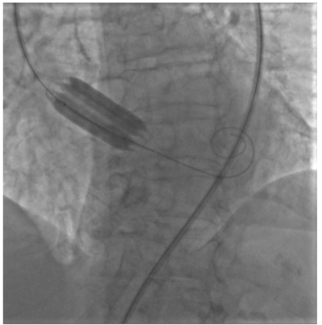

Percutaneous balloon aortic valvuloplasty (BAV) is actually recommended as a bridge to surgery or transcatheter aortic valve replacement in patients with severe aortic stenosis (AS) in particular clinical settings. In this pilot study, for...